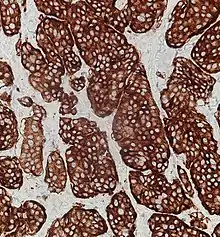

| Micrograph of a neuroendocrine tumor. H&E stain. | |

NETs are often small, yellow or tan masses, often located in the submucosa or more deeply intramurally, and they can be very firm due to an accompanying intense desmoplastic reaction. The overlying mucosa may be either intact or ulcerated. Some GEP-NETs invade deeply to involve the mesentery.[72] Histologically, NETs are an example of "small blue cell tumors," showing uniform cells which have a round to oval stippled nucleus and scant, pink granular cytoplasm. The cells may align variously in islands, glands or sheets. High power examination shows bland cytopathology. Electron microscopy can identify secretory granules. There is usually minimal pleomorphism but less commonly there can be anaplasia, mitotic activity, and necrosis.